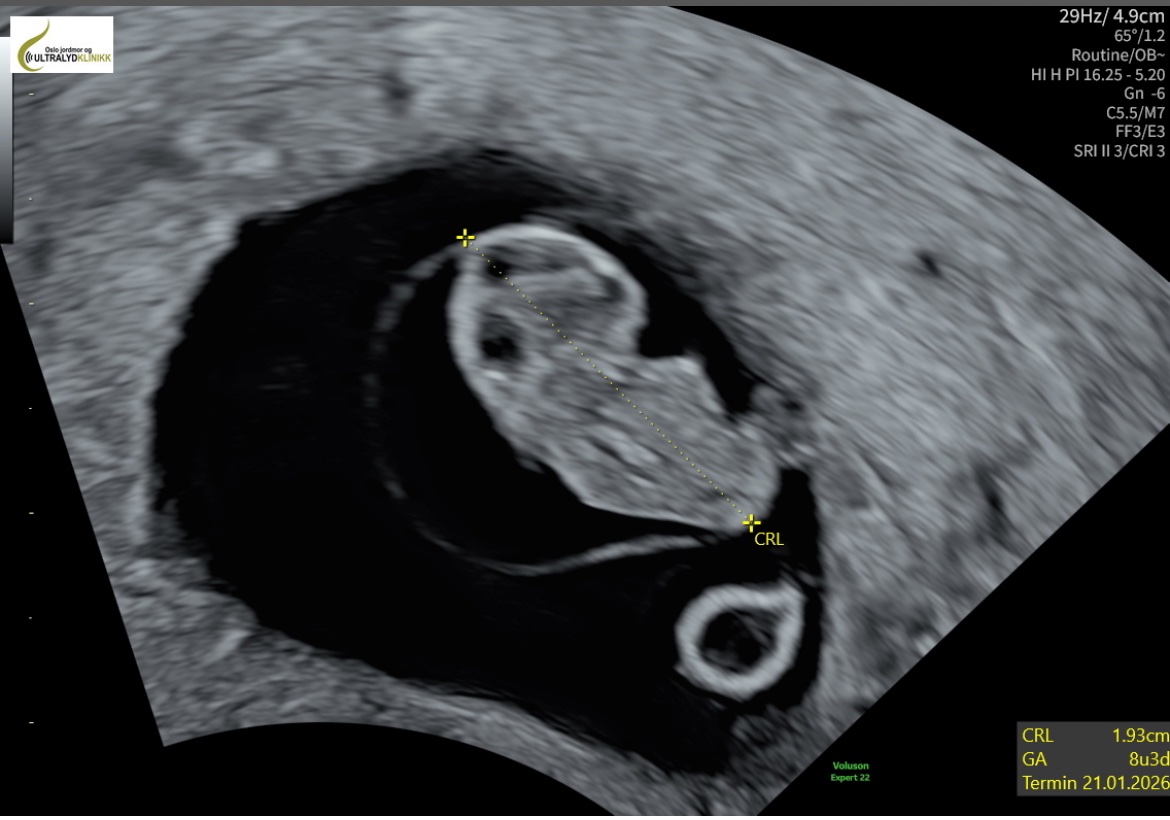

Fikk innkalling til TUL i går, de var superraske! Timen er midt i fellesferien når jeg er 13+2, så det blir noen seige uker. Men hvis jeg tar en ultralyd når vi er tilbake fra utlandet i slutten av juni så skal jeg heller gå til en av de tre stedene jeg allerede har vært